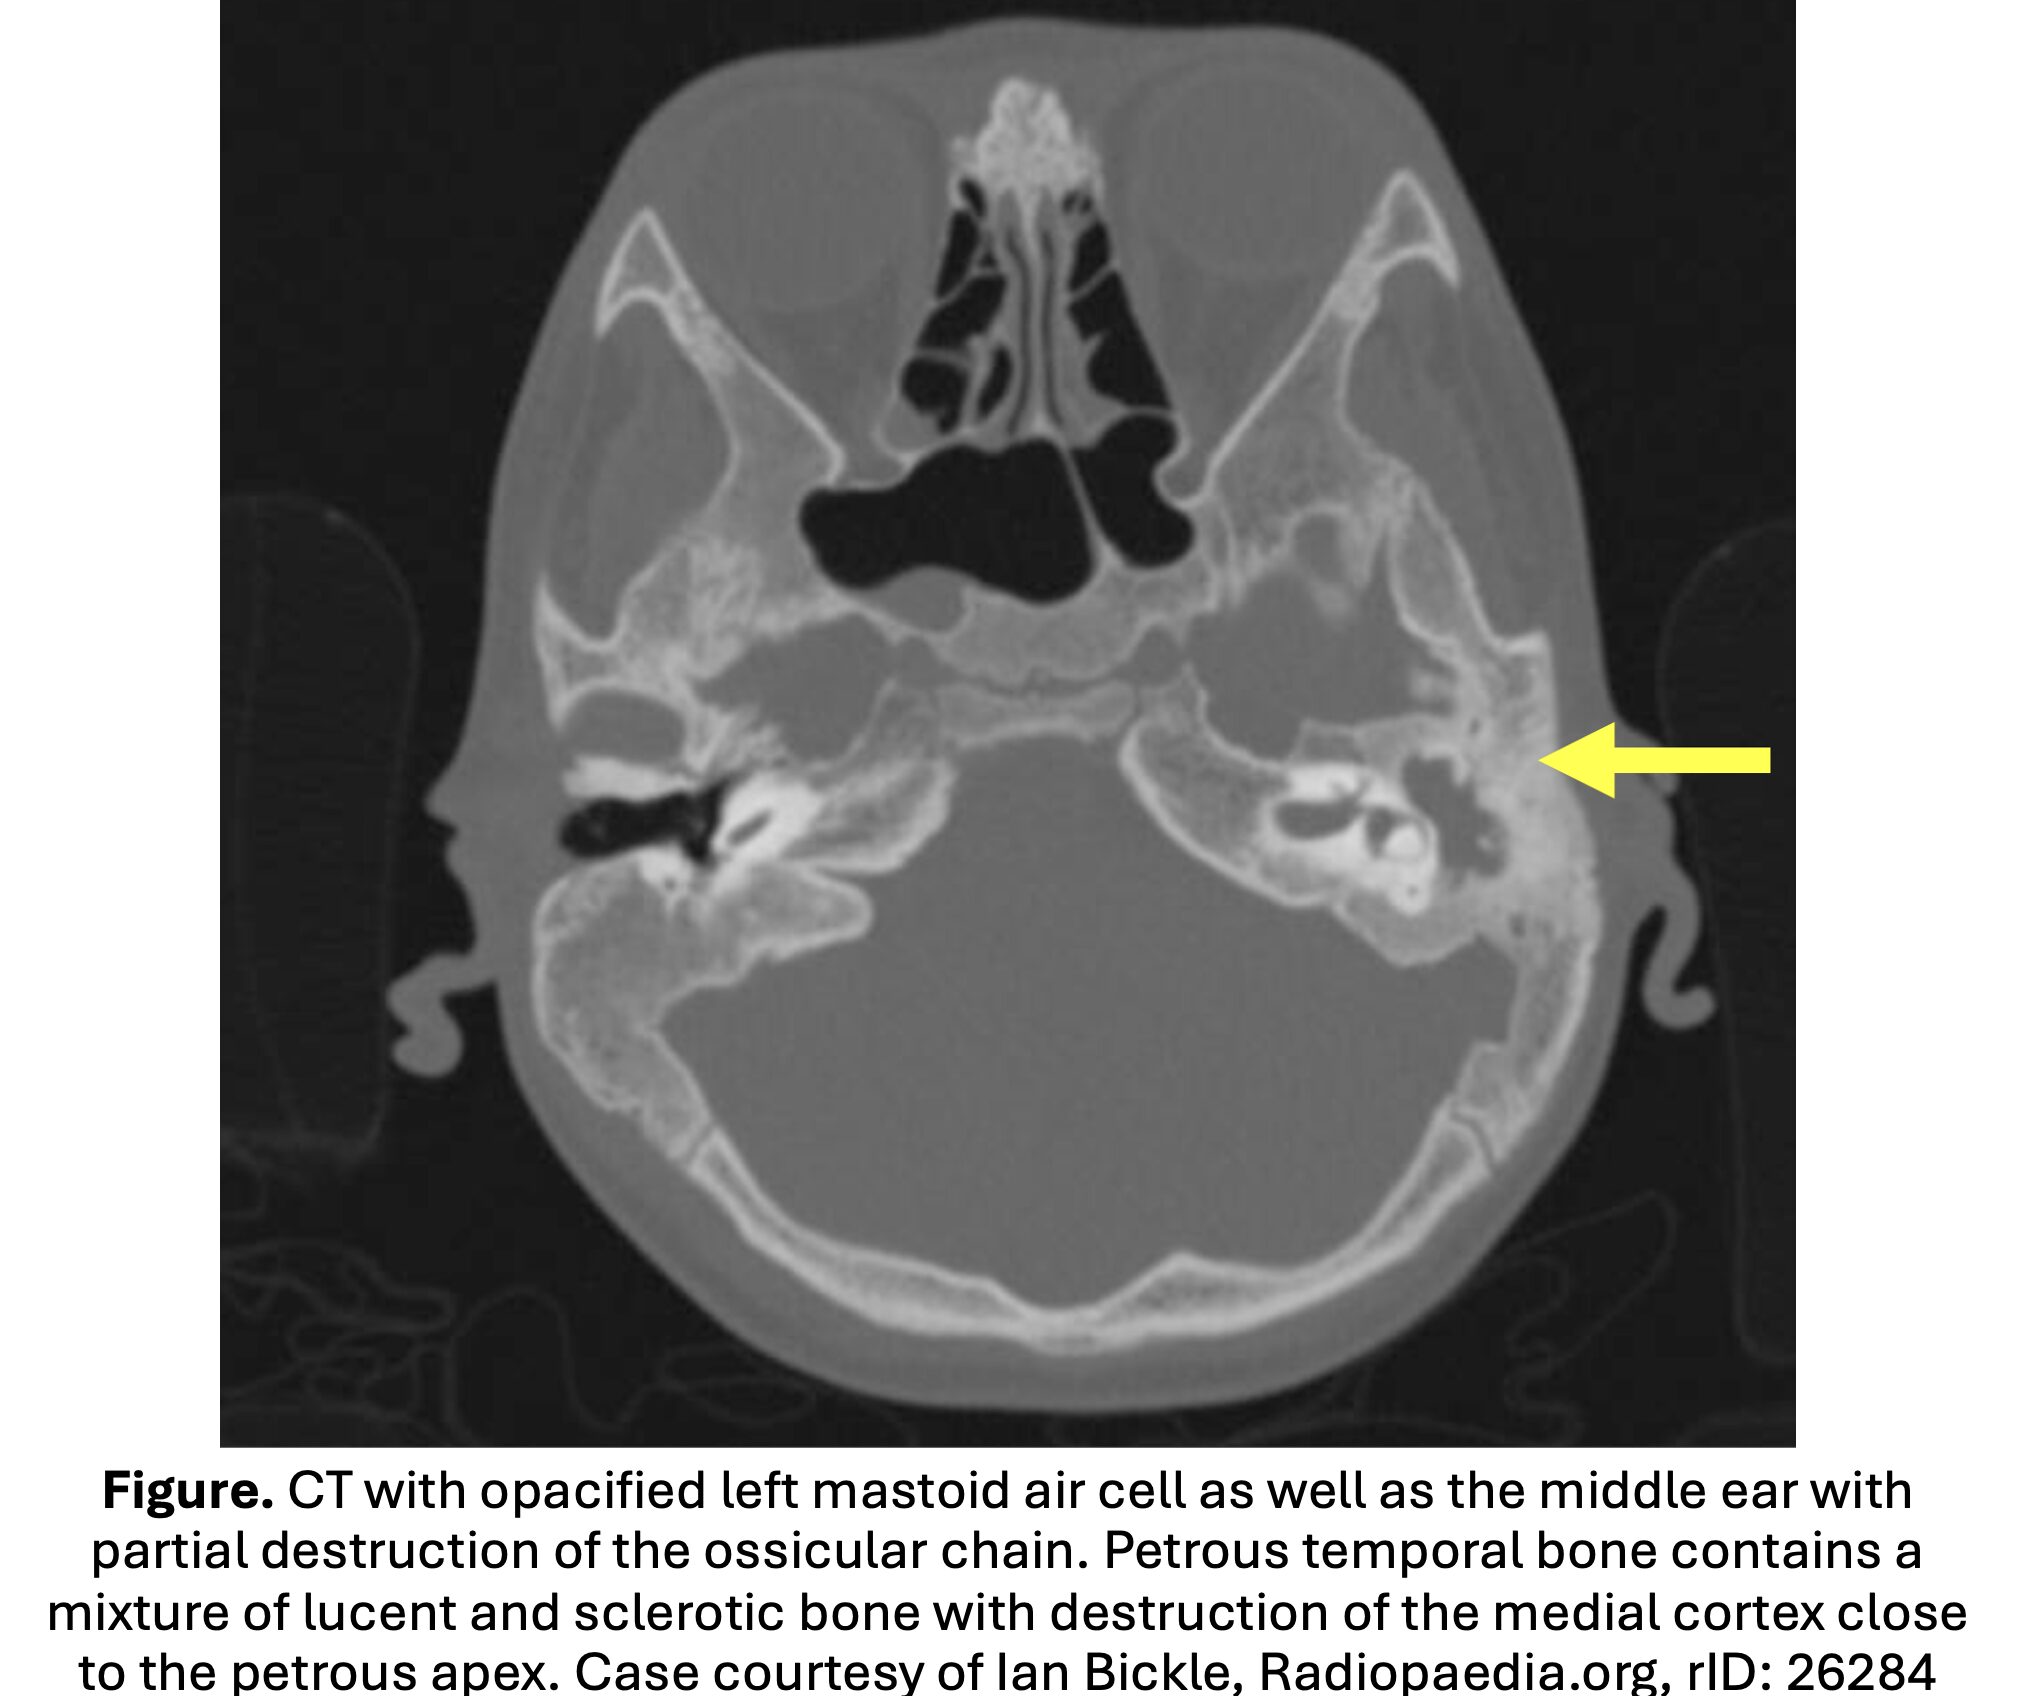

• Diagnostic findings: destruction of the mastoid cortex, periosteal thickening or disruption, and subperiosteal abscess.

• Coalescent mastoiditis: loss of definition in the bony septae defining the mastoid air cells.

• Extracranial complications: subperiosteal abscess (most common complication), Bezold abscess (deep neck abscess), mastoid bony wall destruction, venous sinus thrombosis, labyrinthitis, petrous apicitis, cranial nerve palsies.